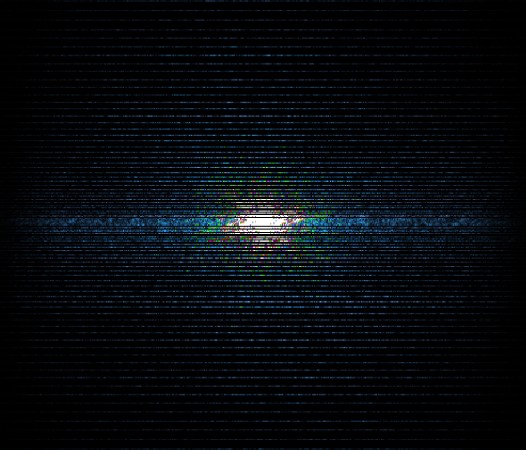

In the example below, only one fifth of the required MR radiofrequency signals is recorded. This results in a five times faster acquisition, with a subsampled k-space (top left) and inherent image artifacts after standard reconstruction (top right).

Basic compressed sensing principle

The Compressed SENSE reconstruction then uses iterative, knowledge-based algorithms to fill in the empty lines in k-space (bottom left). This removes the artifacts while keeping the final image fully consistent with the acquired data (bottom right). *Compared to Philips MR exams without Compressed SENSE